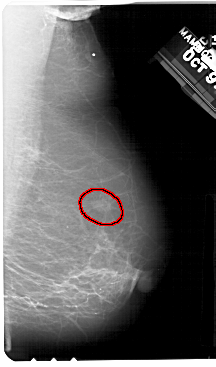

FILE: A_1357_1.RIGHT_MLO.OVERLAY

TOTAL_ABNORMALITIES 1

ABNORMALITY 1

LESION_TYPE MASS SHAPE OVAL MARGINS ILL_DEFINED

ASSESSMENT 4

SUBTLETY 3

PATHOLOGY BENIGN

TOTAL_OUTLINES 1

BOUNDARY